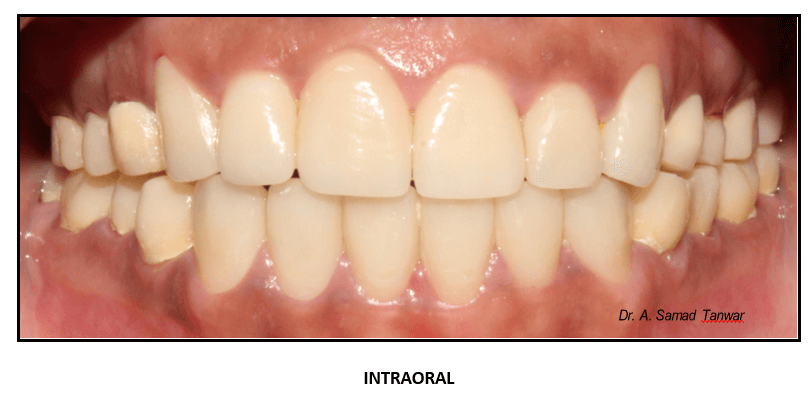

Immediately after post insertion

Occlusal view of the restorations In-situ